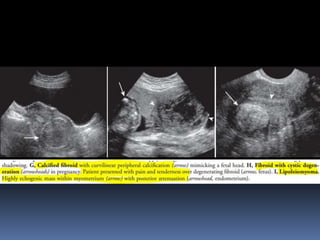

This document contains an image gallery from Dr. Mohit Goel showing various uterine anomalies and ovarian cysts. It includes images of an arcuate and unicornuate uterus, endometritis, a twisted ovarian pedicle, dermoid cysts of varying sizes and echogenicity containing hair, fat, and calcifications, and a combination dermoid cyst showing both mesh and plug structures. The gallery provides ultrasound images of different gynecological conditions for medical education and reference.